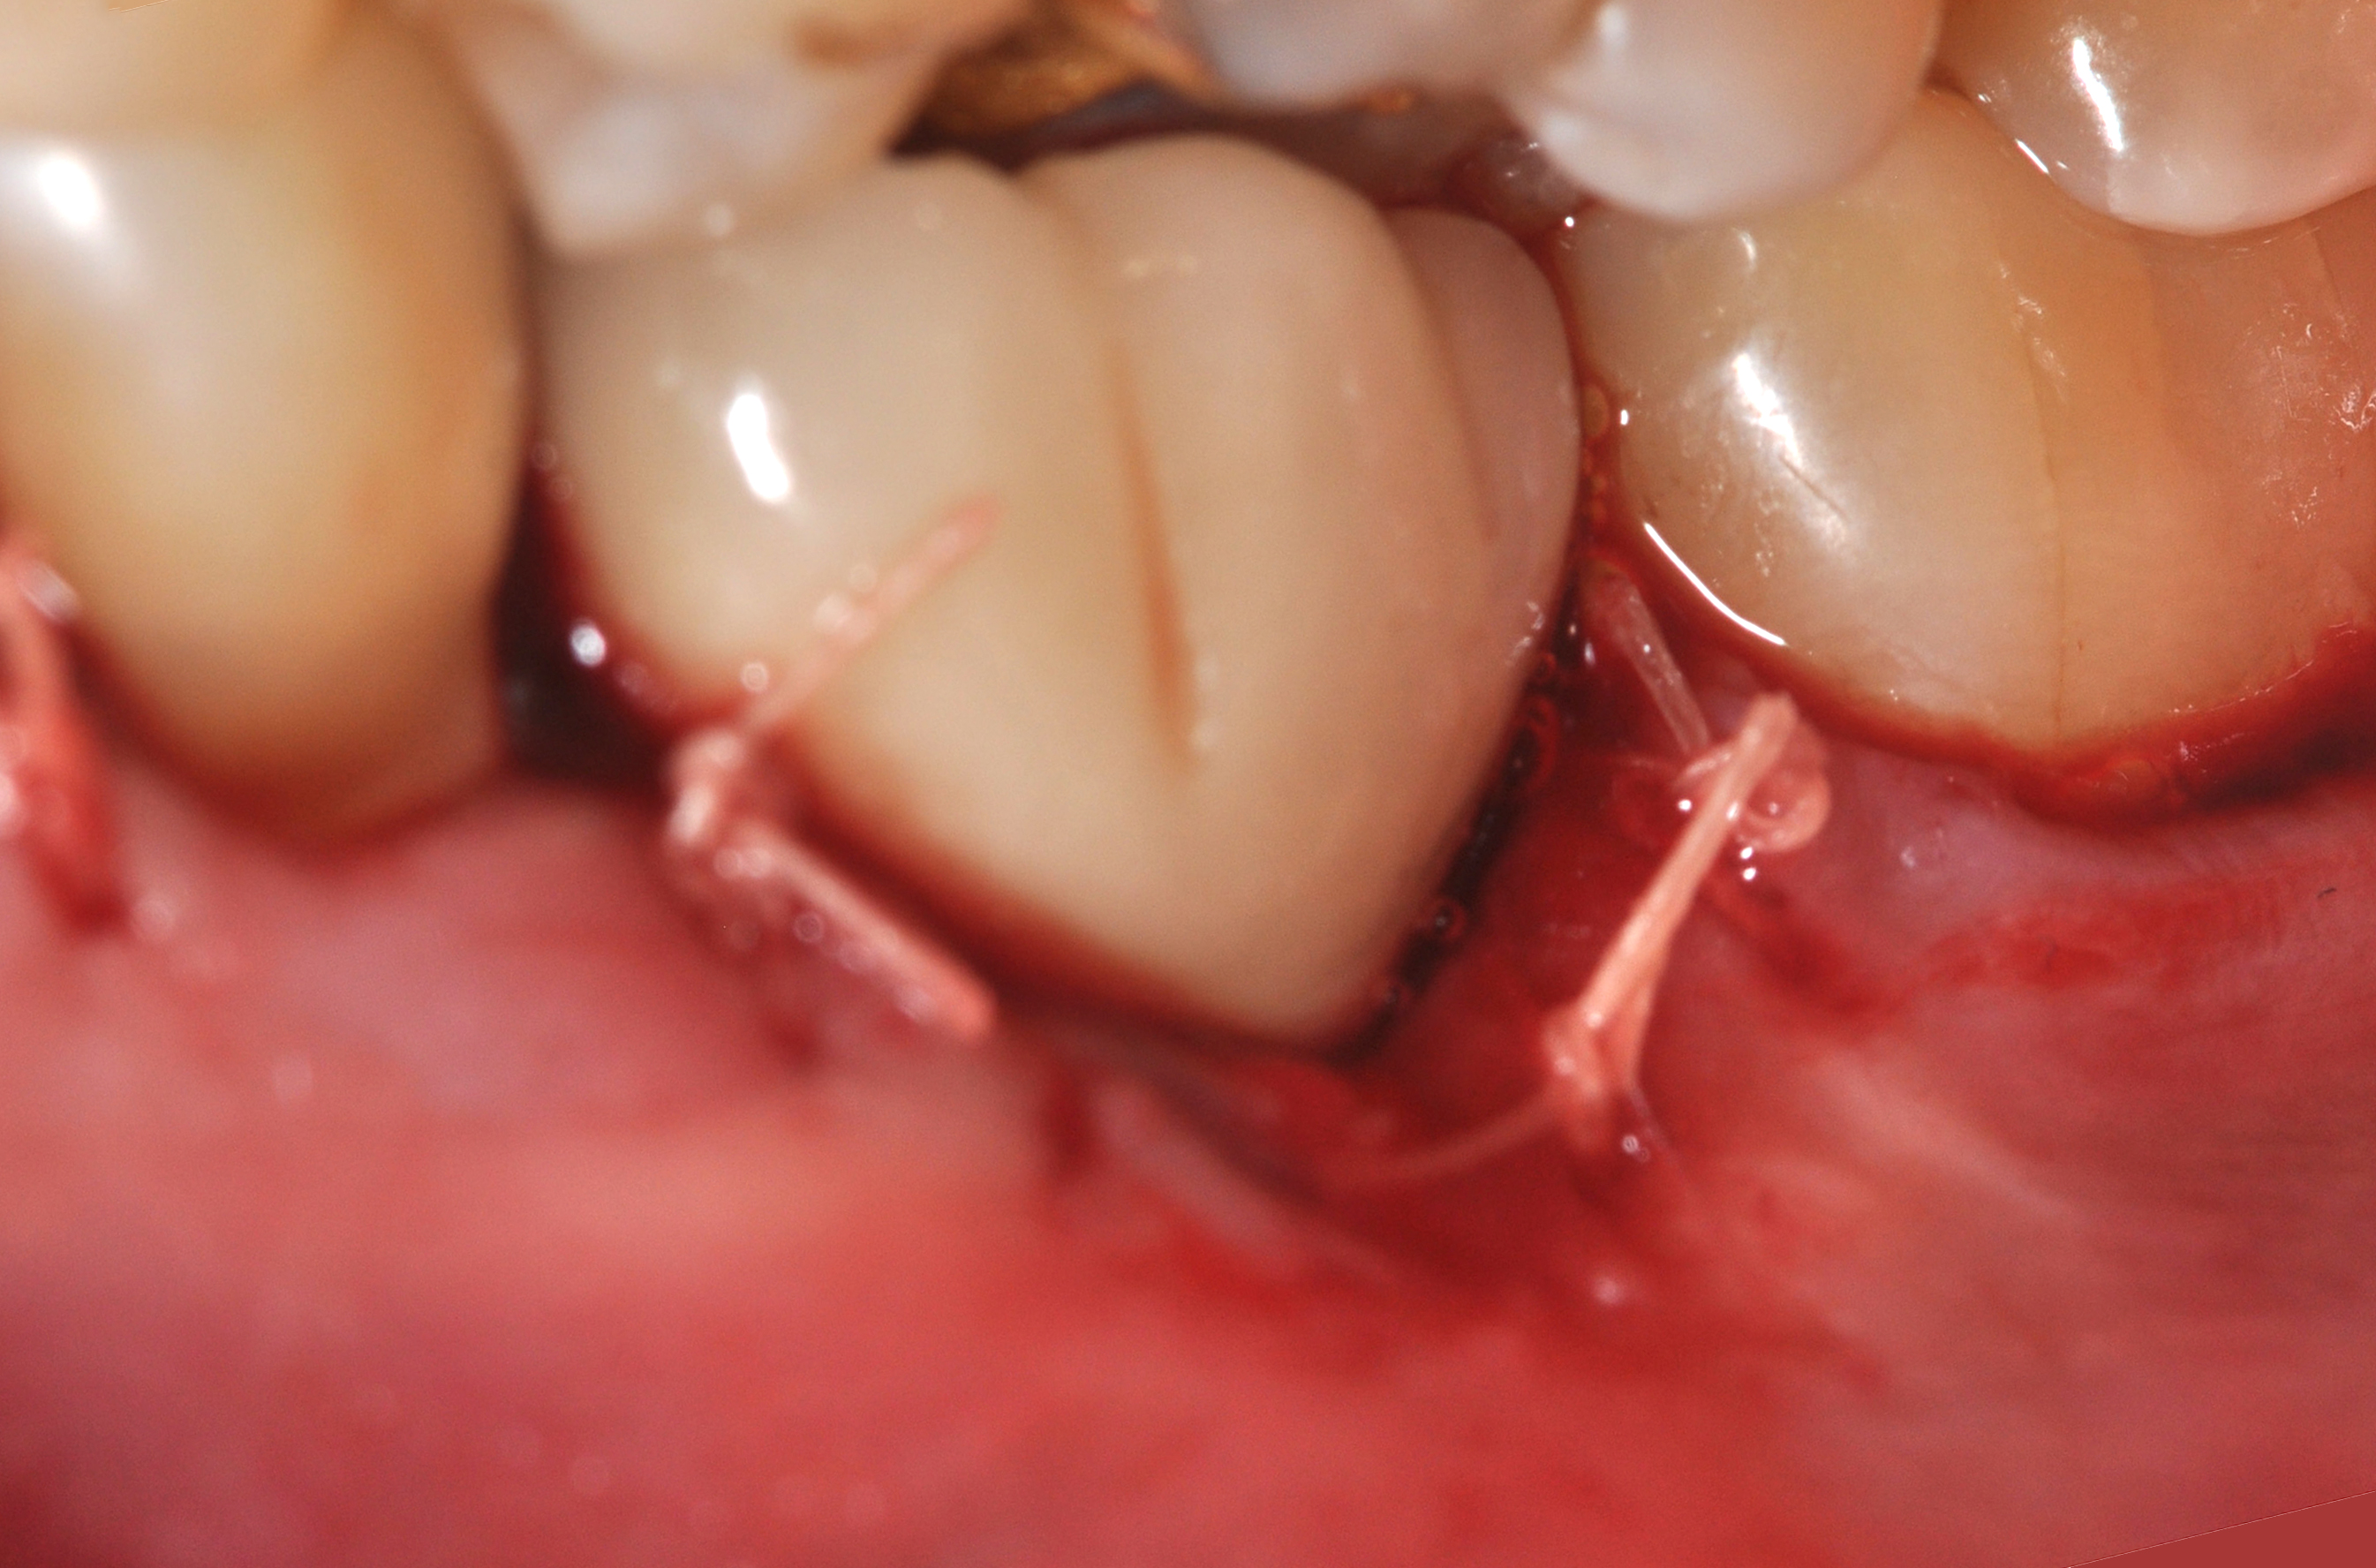

Fig 18. A full-thickness flap from teeth Nos. 18 to 20 revealed granulomatous tissue in the circumferential defect around implant No. 19.

Figure 18

Fig 19. The circumferential defect was debrided. Note excess cement extending apically from the margin of the crown into the defect; residual cement has been shown to be complicit in the development of peri-implant disease.

Figure 19